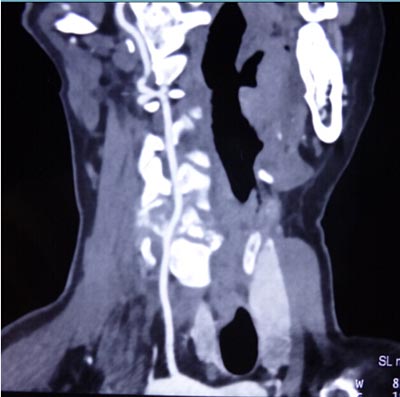

近日,我院骨二科成功完成一例前后联合入路颈椎肿瘤切除重建术。该患者来自陕西汉阴,女,45岁,1月前无明显诱因感颈肩部疼痛不适,在当地医院就诊行相关检查诊断:“颈5椎体病理性骨折”,考虑手术的风险及难度极高,建议转至我院。磁共振检查示“颈5椎体及附件破坏并塌陷”,椎动脉血管造影示“右侧椎动脉发育不良,颈5椎体及附加破坏并包绕椎动脉”。积极术前准备工作,全科讨论后制定前后联合入路肿瘤切除重建手术方案。手术于2014.10.20日如期进行,张晓琴教授负责麻醉,术中进行动脉血压监测、中心静脉压监测、动态血气分析、全面的的生命体征监测,确保了手术安全和平稳。手术由李浩鹏教授指导,王栋副教授主刀,赵波主治医师协助。先取颈部前侧入路,于气管鞘及食管鞘间隙进入,切除颈5椎体,术中可见颈5椎体破坏,彻底切除病变组织至双侧横突,显露椎动脉及神经根,小心完整切除右侧椎动脉包绕的鱼肉样病变组织,更换手套,取左侧髂骨修剪为颗粒状及短棒状置入钛网放置于颈5椎体缺损部,前方钛板固定进行重建。再取俯卧位,颈部后正中切口,彻底切除颈5棘突及双侧椎板至双侧横突,双侧侧块钢板固定。手术顺利,术前症状显著改善,术后第二天即可在颈托保护下下地活动。该部位解剖复杂,血管、神经多,不易分离,有可能损伤椎动脉,脊髓及神经根,引起截瘫、大出血,脑坏死等,风险很大。术中以最精准的操作,解剖性、根治性切除病灶,同时进行了骨性重建,保证了颈椎的稳定性。该肿瘤的成功切除及重建,显现了我院骨二科的综合技术实力,以及团结协作、严谨求实、不断进取的专业精神,也标志着我院的脊柱外科达到国内先进水平。